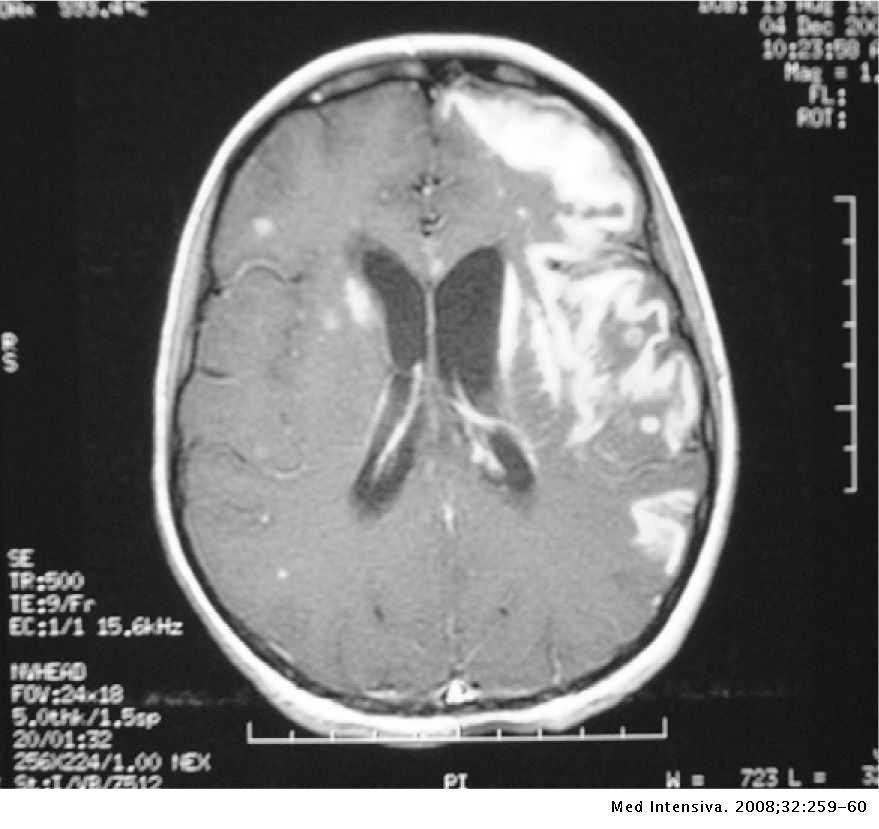

La imagen puede verse normal en meningitis, V/F:

Verdadero

¿Qué vamos a encontrar en la TC de meningitis?

¿Cuál es el mejor estudio de imagen para la meningitis?